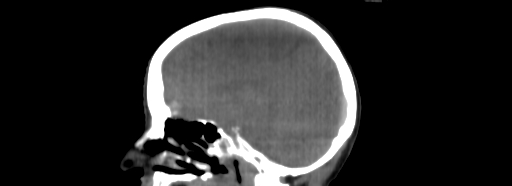

ClearRT® Images

Imaging Information

ClearRT®

Protocol

Brain-fineFOV27cm Whole body-mediumFOV 50cm

Scan Length

16cm

KVCT Imaging Time

20 sec